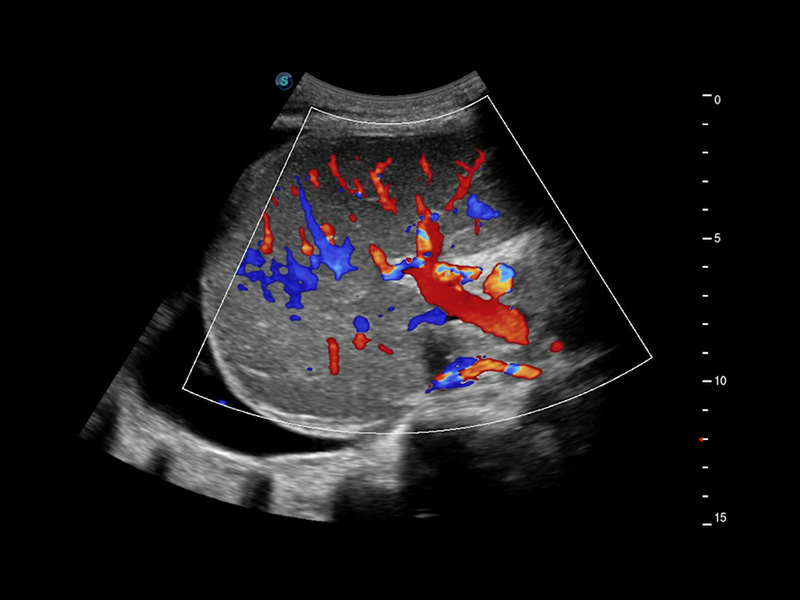

Micro F

Consente la visualizzazione delle strutture microvascolarizzate

Micro F offre un metodo innovativo per ampliare la portata di flusso visibile nell'ecografia, in particolare per visualizzare l'emodinamica dei piccoli vasi a flusso lento. Grazie all'adozione di un filtro adattivo avanzato e all'accumulo di segnali temporali e spaziali, Micro F è in grado di distinguere in modo efficace il flusso minuto dal movimento di tessuto sovrapposto e di rappresentare l'emodinamica con sensibilità e risoluzione spaziale più elevate.

• Arteria pericallosa fetale con Micro F

• Flusso ematico renale con Micro F

• Nodulo tiroideo con Micro F

• Linfonodo cervicale con Micro F